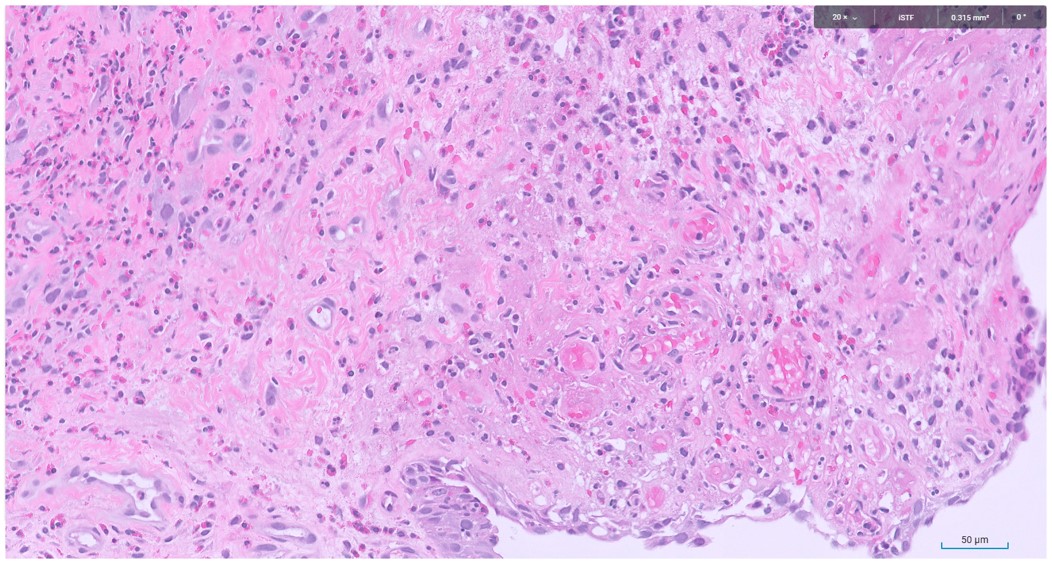

Microscopic image possibly detecting cancerous areas in human tissue

What is the most likely diagnosis?

1. Radiation cystitis

2. Cystitis cystica

3. Invasive urothelial carcinoma

4. carcinoma in situ

Radiation cystitis